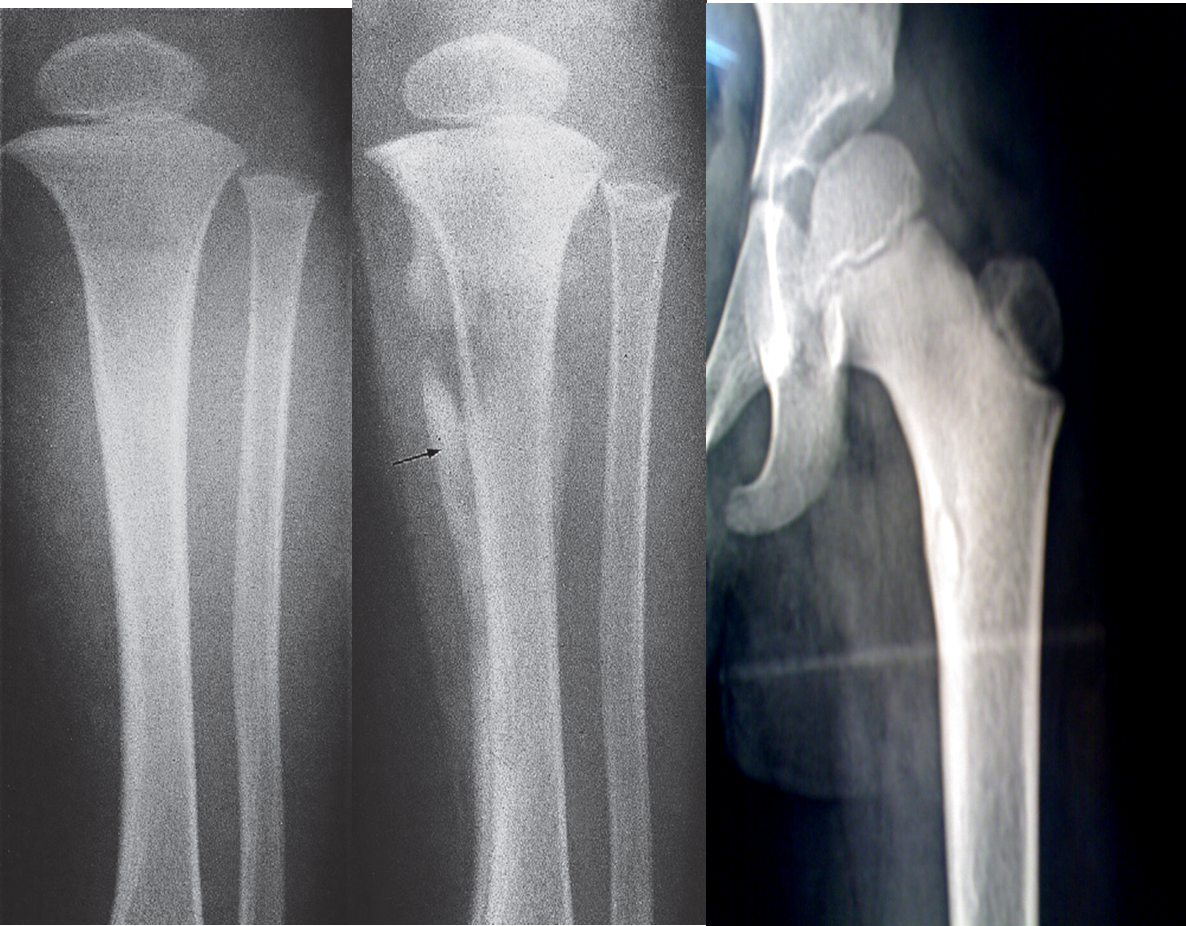

Compare X-ray and MRI in this case of acute osteomyelitis.

- It is difficult to be seen on plain x-ray.

- The extent of disease is well demonstrated by MRI

(A) Â An initial films reveals no abnormality

(B) A film taken 3 weeks later shows some destruction of the upper end of the tibia and an extensive periosteal reaction along the tibia, particularly the medial side (arrow).

(C) Bony sequestrum X-ray leg (left; AP view) of a child A fragment of bone has separated from adjacent bone and is surrounded by a lucent rim. chronic osteomyelitis.Â